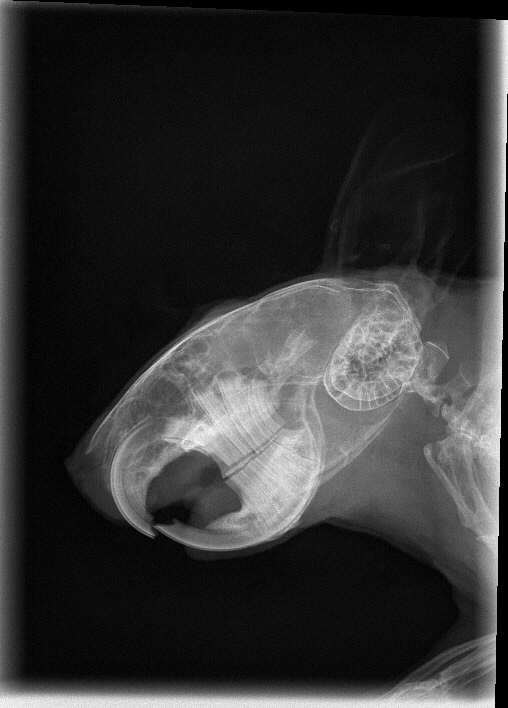

Wir haben ein ähnliches Bild von unserer damals 7 jährigen Fibi... ich bin zwar weit entfernt von einem Fachmann und kann aus Röntgenbildern herzlich wenig rauserkennen, aber dieses Foto haben wir damals einer TÄ der Tierklinik der LMU geschickt, die sich auf Degugebisse spezialisiert hatte und sie meinte, die Zähne schauen sehr gut aus.